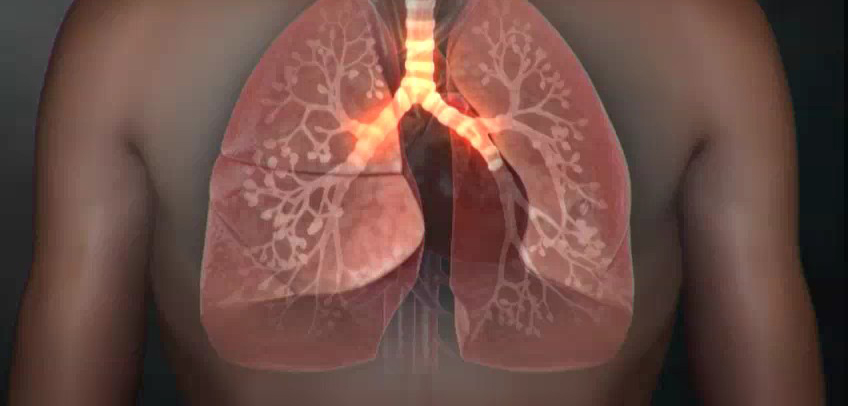

9. 흉부 고통

폐암에 걸리면 흉부에 고통이 느껴져요. 폐의 가장자리에 생긴 폐암이 흉막과 흉벽을 침범해서 고통이 생기는 것으로 가슴이 답답하면서 꽉 막힌 느낌이 지속되며 날카롭게 찌르는 듯한 느낌과 압력 하는 느낌 등 여러 가지 고통이 나타납니다.